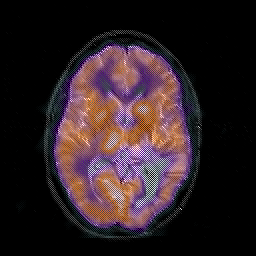

Glioblastoma multiforme overlay -- Slice #28

[Home][Help][Clinical][Tour 1][Tour 2][Tour 3] Slice 28